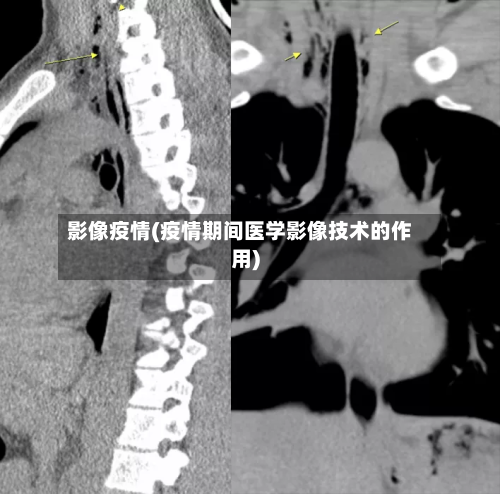

是的,您的CT片有可能由AI医生来读取 ,近来已有新冠肺炎CT影像AI筛查系统应用于医院,辅助医生进行诊断。以下是对该AI系统的详细介绍:系统研发与应用:南开大学计算机学院与北京推想科技联合研发了新冠肺炎CT影像AI筛查系统,该系统已在包括湖北在内的国内40家医院应用部署 。

胸部CT检查若报告十几个或几十个肺结节 ,确实很可能是人工智能(AI)技术过度识别导致的,这些结节大多无临床意义,无需过度焦虑或频繁复查。具体分析如下:AI技术的优势与局限性AI技术凭借高灵敏度,可检测出医生可能遗漏的微小肺结节 ,尤其在查漏补缺方面具有显著优势。

不同医院CT导入AI读片的时间存在差异,具体如下:献县中医院:CT室于2023年引入并开展人工智能(AI)影像辅助诊断应用技术 。这一举措标志着该院在医学影像诊断领域迈出了重要一步,通过AI技术的辅助 ,能够更快速、准确地识别影像中的异常,为临床医生提供更可靠的诊断依据。